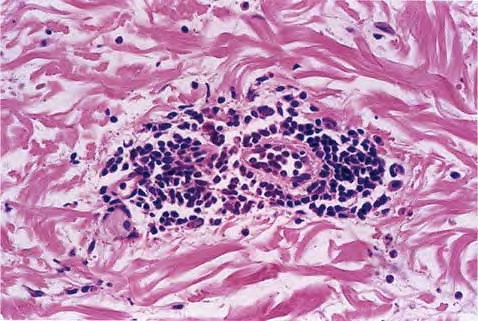

Erythema Chronicum Migrans =الحمامى المزمنة الهاجرة